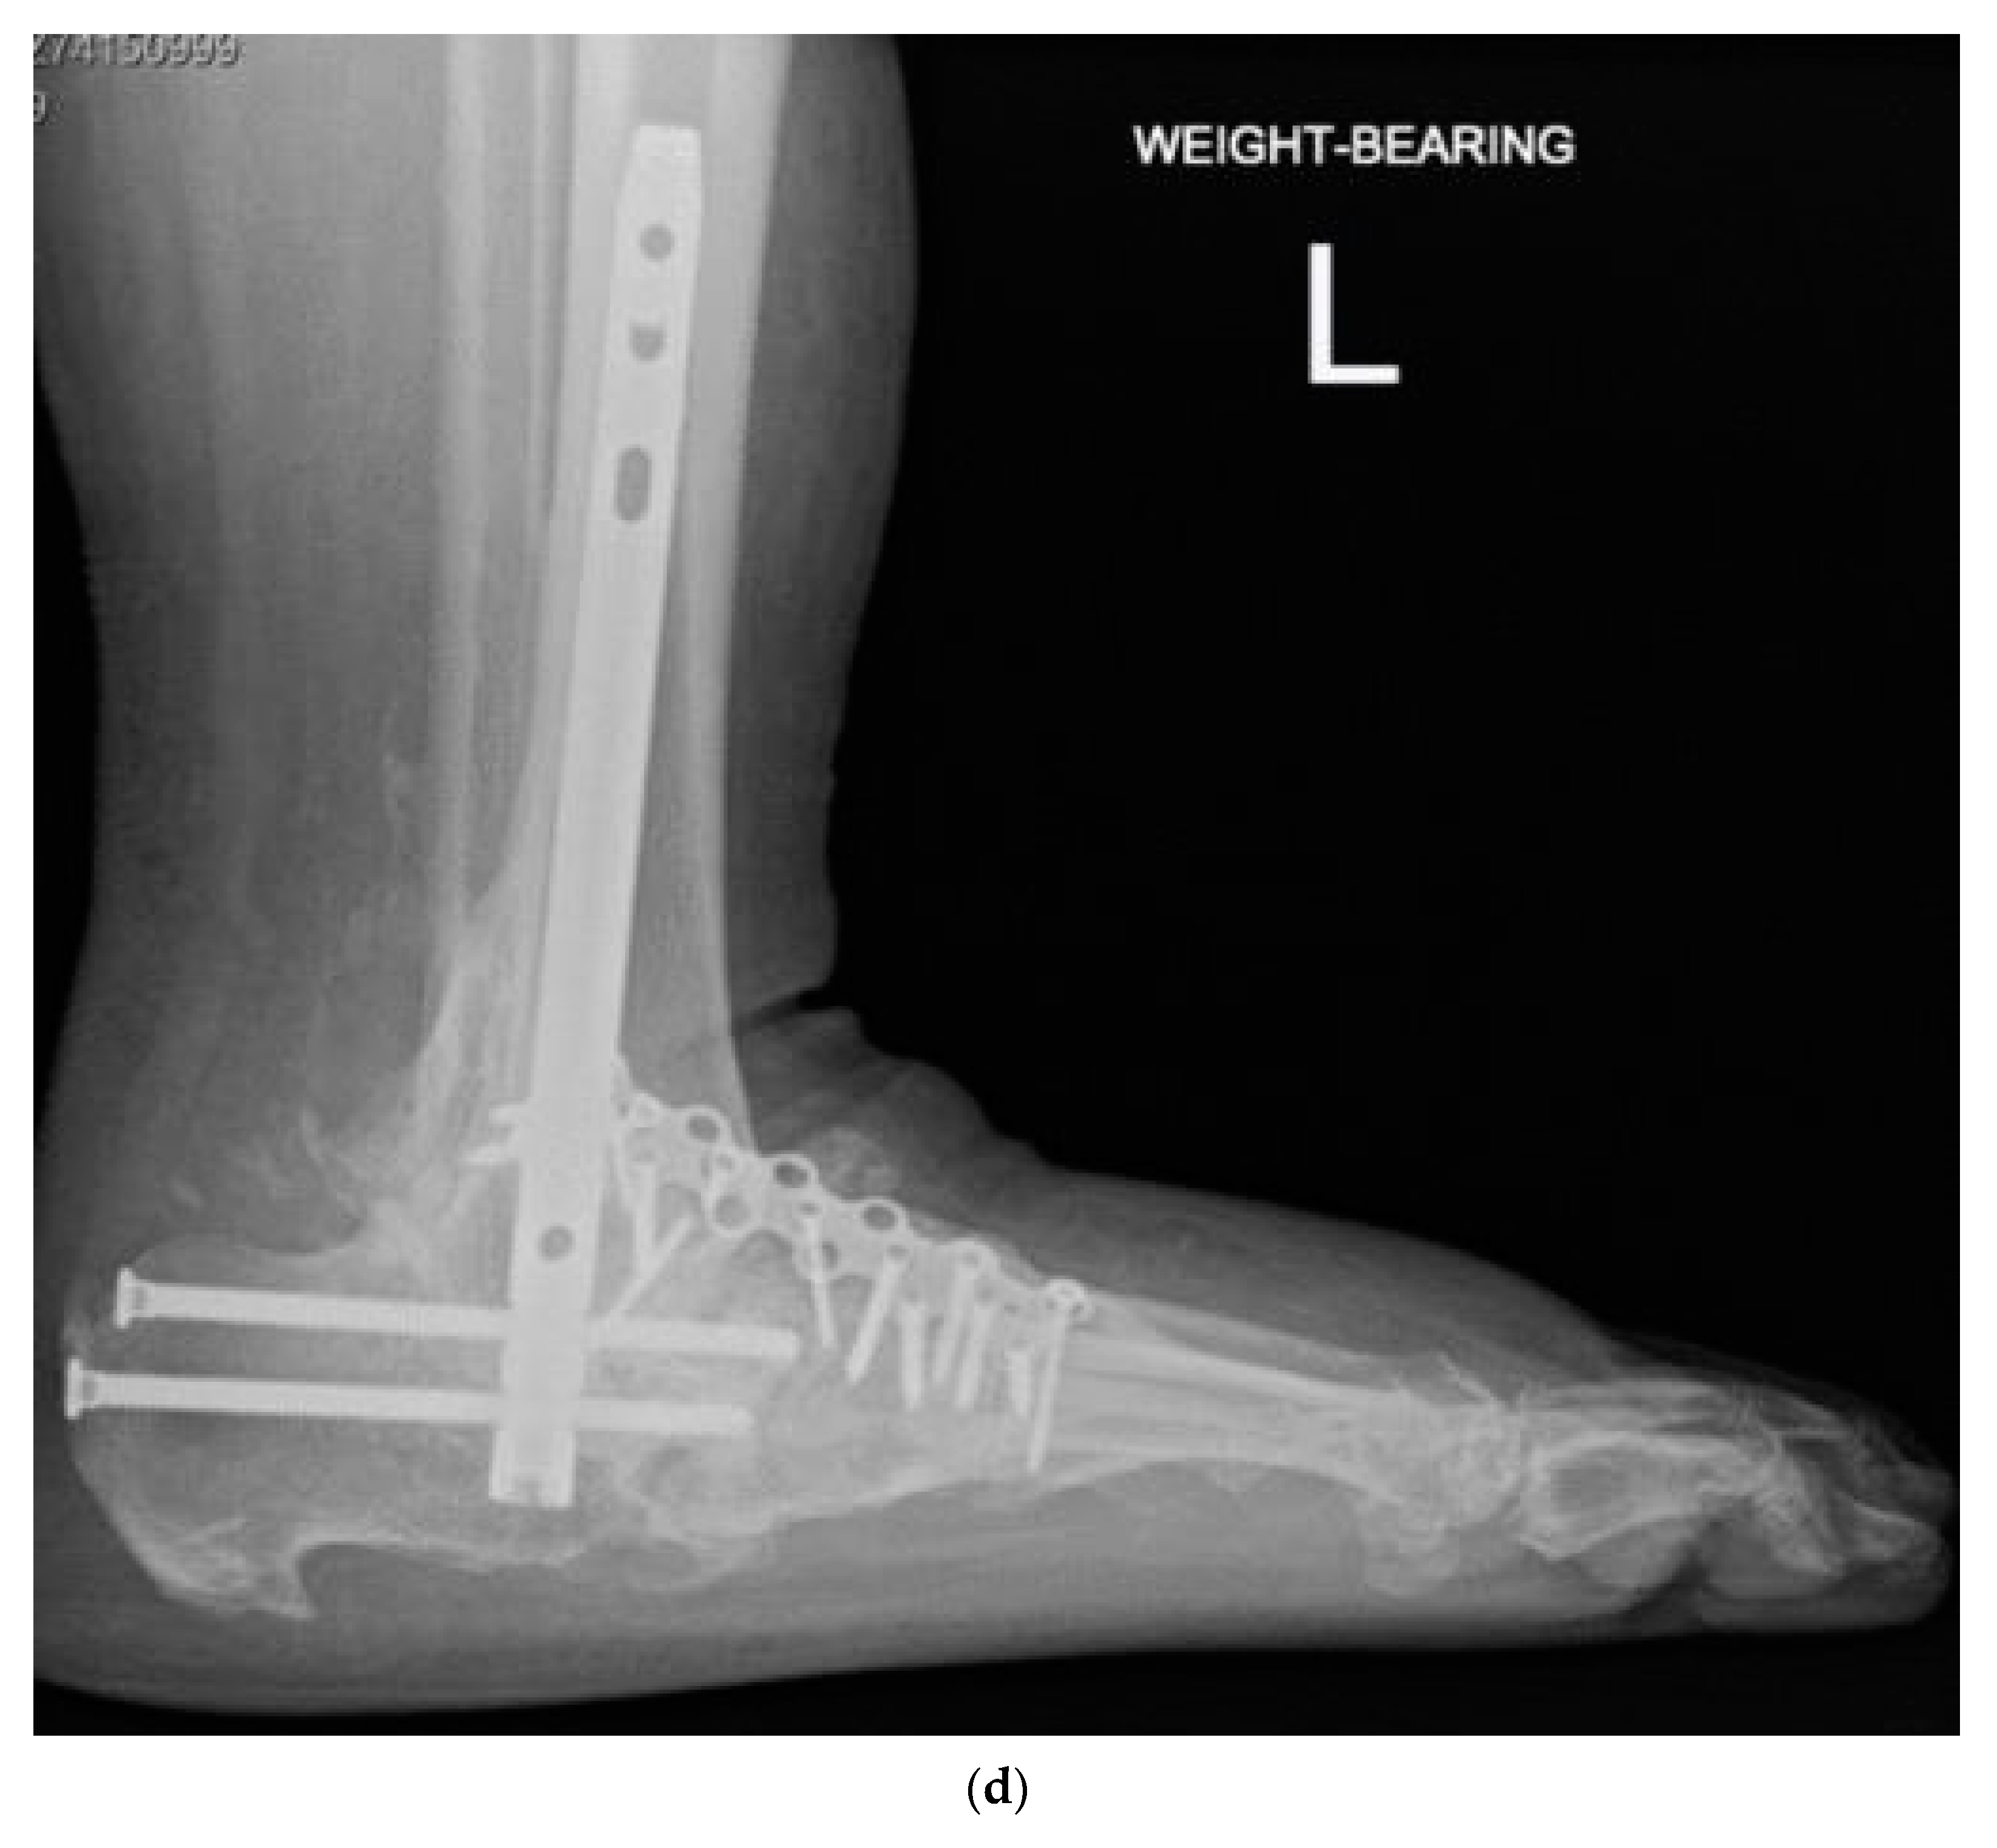

2.4. Surgical Management

- Siebachmeyer, M.; Boddu, K.; Bilal, A.; Hester, T.W.; Hardwick, T.; Fox, T.P.; Edmonds, M.; Kavarthapu, V. Outcome of one-stage correction of deformities of the ankle and hindfoot and fusion in Charcot neuroarthropathy using a retrograde intramedullary hindfoot arthrodesis nail. Bone Jt. J. 2015, 97, 76–82. [Google Scholar] [CrossRef] [PubMed]

- Vasukutty, N.; Jawalkar, H.; Anugraha, A.; Chekuri, R.; Ahluwalia, R.; Kavarthapu, V. Correction of ankle and hind foot deformity in Charcot neuroarthropathy using a retrograde hind foot nail-The Kings’ Experience. Foot Ankle Surg. 2018, 24, 406–410. [Google Scholar] [CrossRef]

- Kavarthapu, V.; Hester, T. Charcot hindfoot deformity reconstruction using a hindfoot nail—Surgical technique. J. Clin. Orthop. Trauma 2021, 16, 277–284. [Google Scholar] [CrossRef] [PubMed]